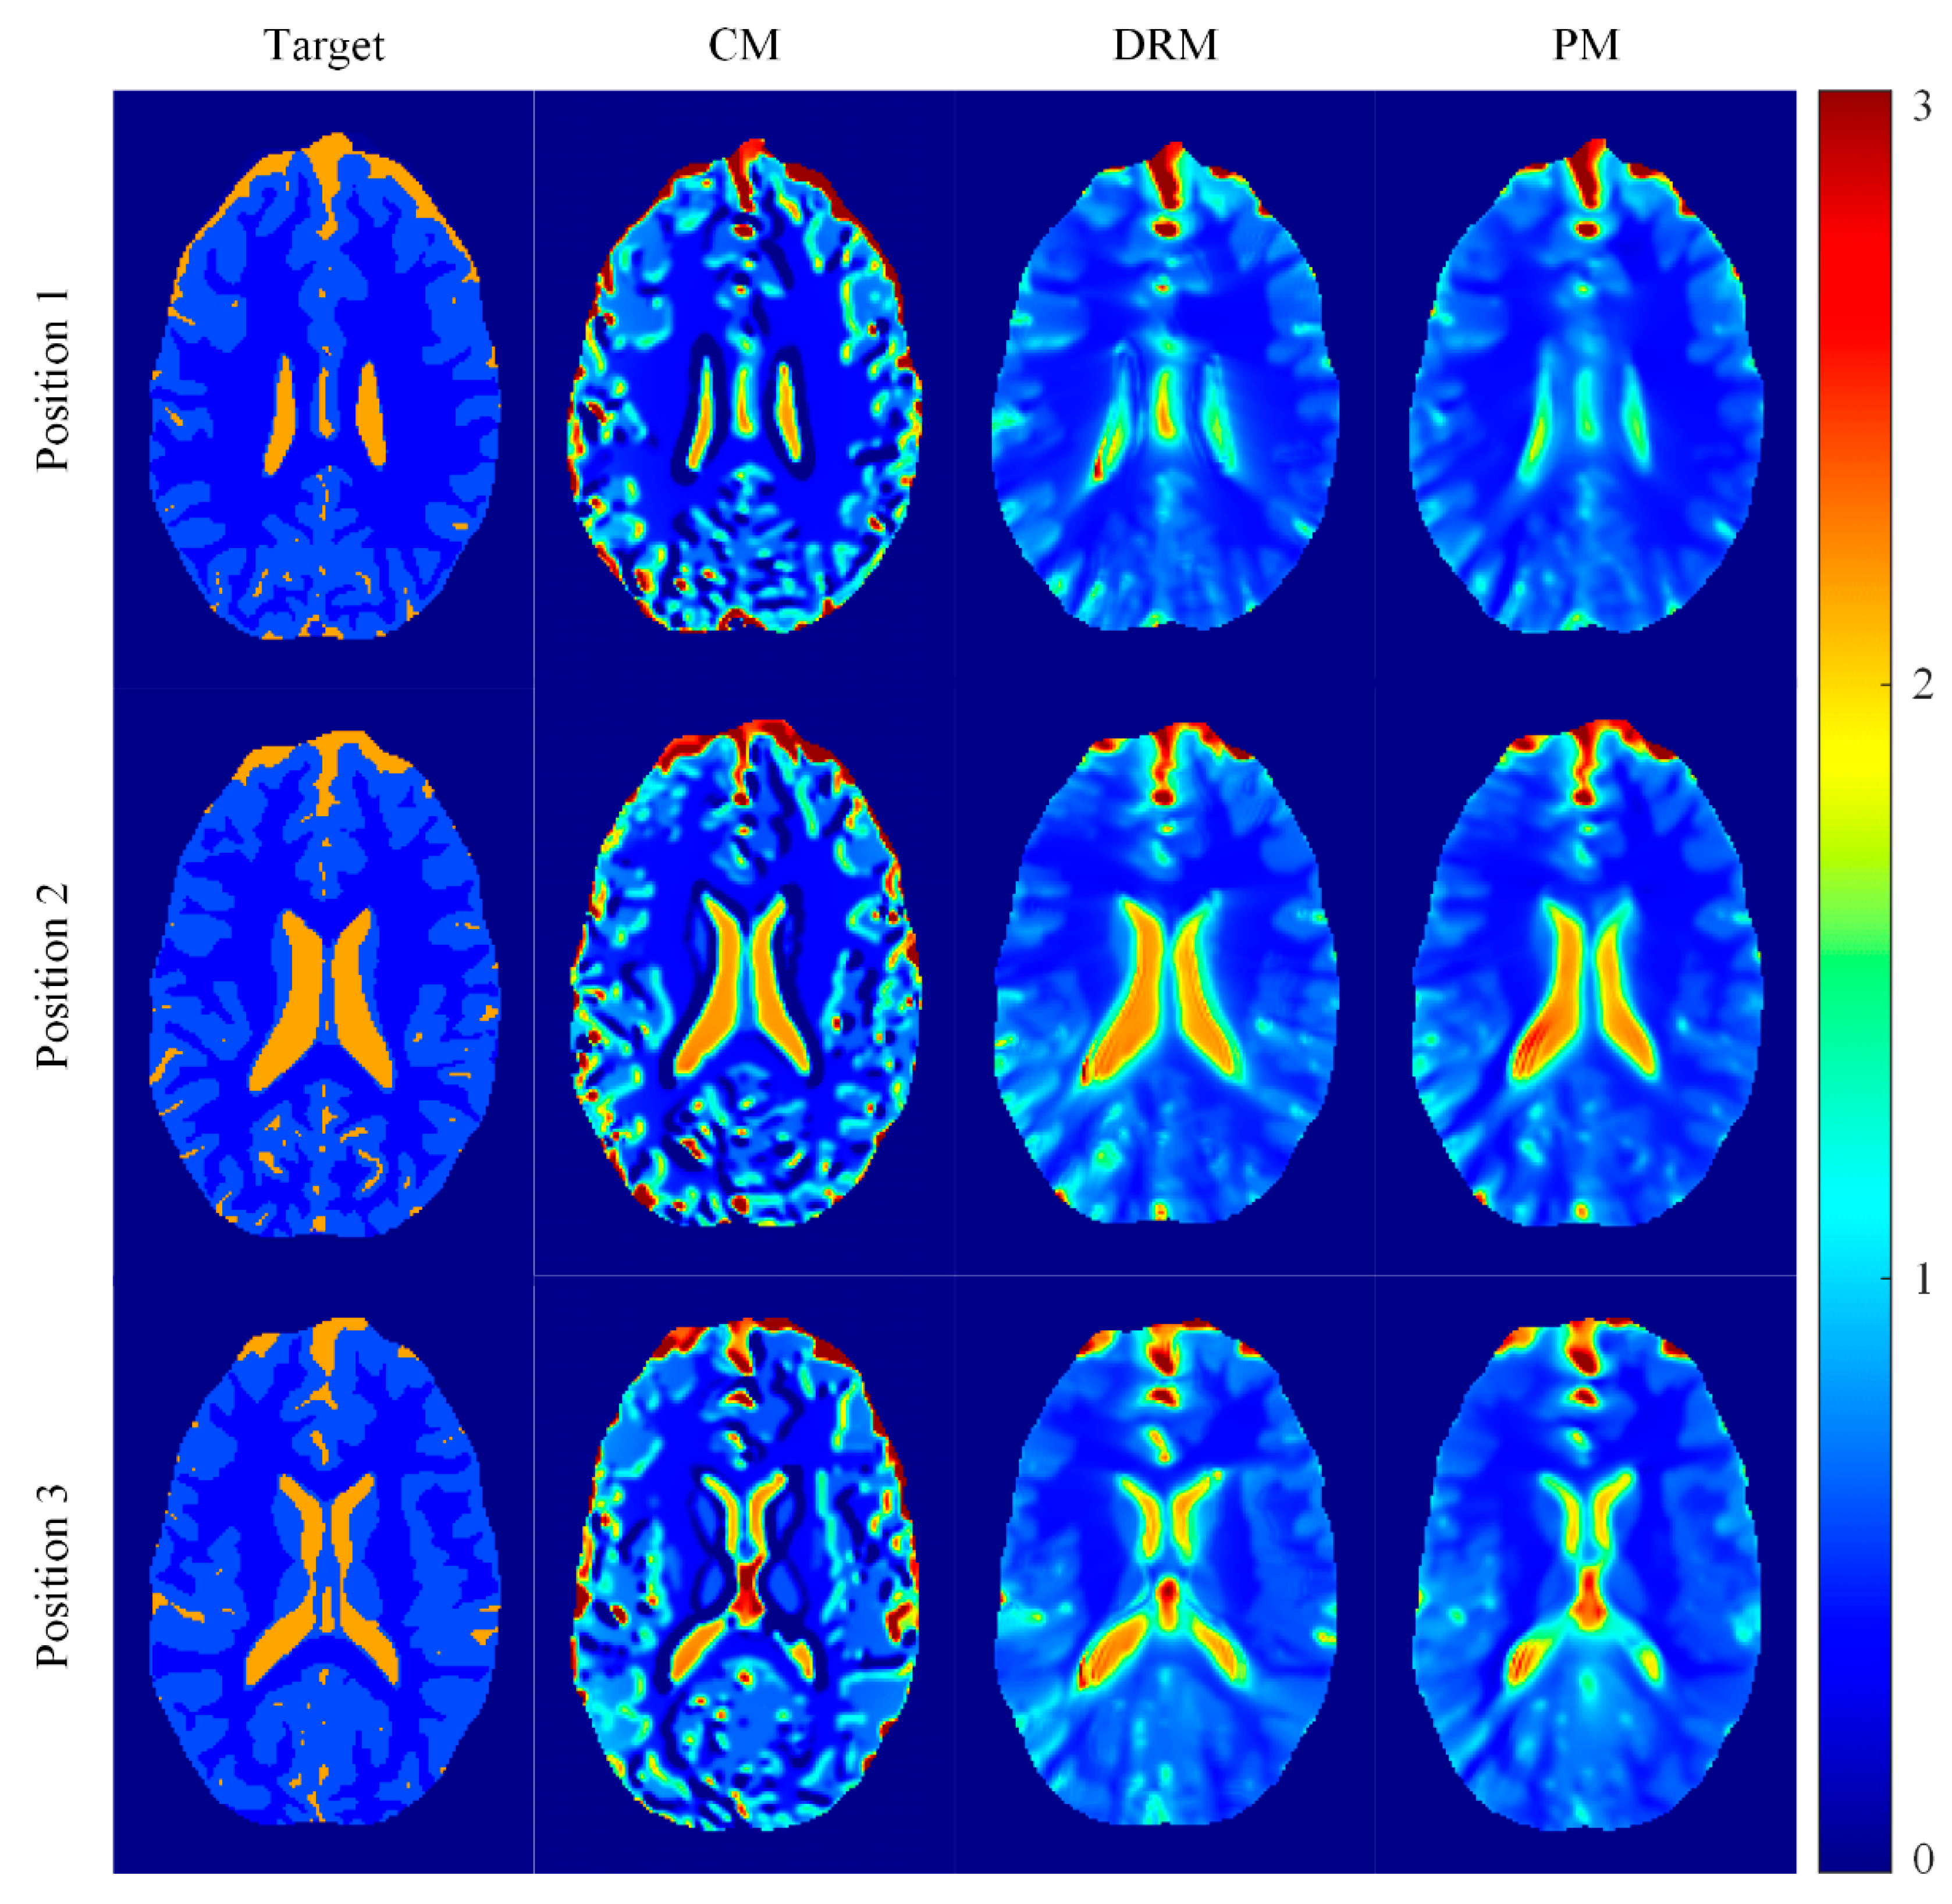

4.1. Phantom Simulation Results

4.2. Ella Head Simulation Results